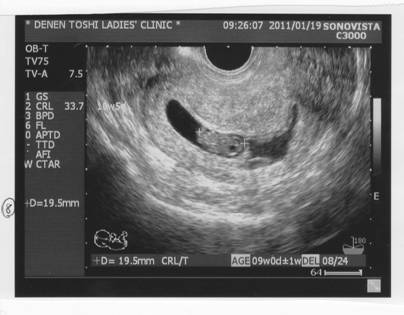

内診。

出血はまだ認められる。

しかし19.5mmと大きさ的には問題なく、成長はしている。

との事。ひしゃげて見えるのが気になったが、

「エコーの向きだろう。それは心配ない。」との事だったそう。

確かにひしゃげて見える・・・。

「現在、成長は順調だが、出血があり4ヶ月で胎盤が安定するまではどうなるかわからない」

という前回からの診断そのまま、変更はなかった。

帰宅後、すぐにエコー写真を見る。

・・・確かに、心配になるのもよくわかるな。

ネットで検索すると・・・角度によって、確かに見え方は違うようだ。

そして大丈夫なヒトは「バナナ型」でも「サンダル型」でも「ヒトデ型」でも問題なく出産に至っているし、

逆に何か疾患があるなどして、ダメになる過程で潰れて見えることもある。

トイレを我慢し子宮が膀胱で押されてひしゃげて映った、なんてのもあった。

つまり、潰れて映っていても、

エコーの胎のうの形だけで「大丈夫」「危ない」という判断基準にはならないってこと。

やはり「胎盤形成が安定する4ヶ月」に注力するしかないと思う。